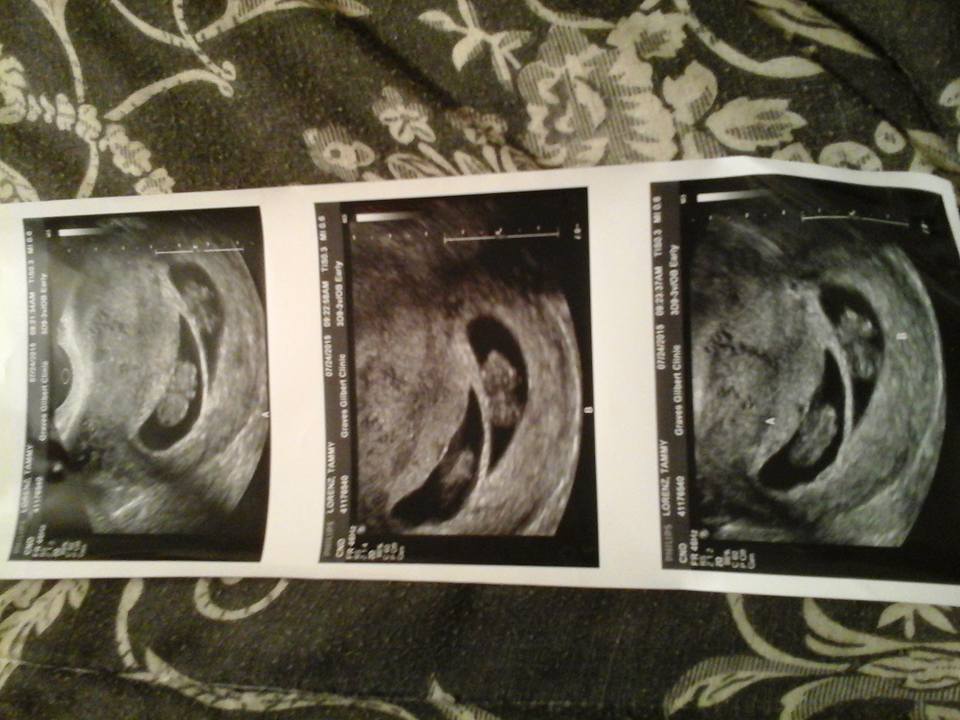

@pdtoast, great photos!! Are you team green? just wondering b/c according to the nub theory, it is very much obvious the sex of your LO.

Nope, we'll find out. I'm not familiar with that theory, but the US tech said that her guess would be boy although she emphasized that it's too early to make a definitive statement about sex. Not sure if that's what you were thinking too.

Yeah... I would be shocked if it's not a boy.